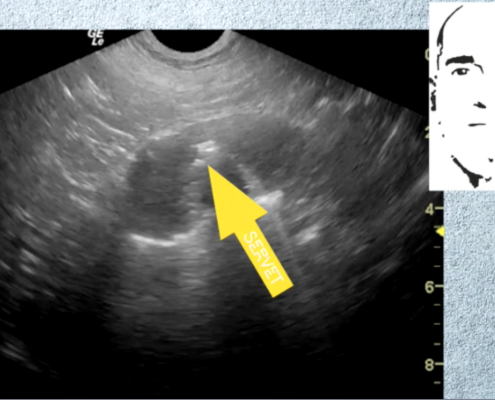

Servet, como Centro de Referencia, se mantiene al día de todas las novedades que afectan al desarrollo de nuestras actividades, con dos objetivos principales, mejorar la formación del personal clínico e incorporar los medios tecnológicos más avanzados. Esto nos permite mejorar el bienestar de los animales atendidos.